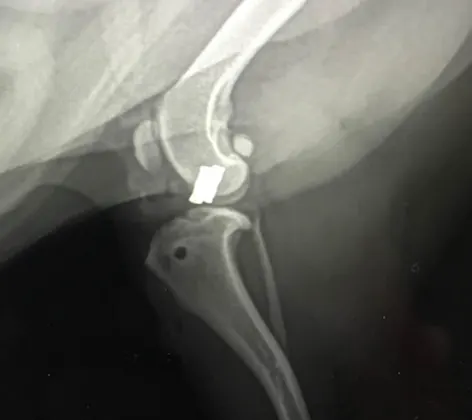

TPLO Surgery

Clinical signs of CrCL tear in dogs range from intermittent limping to acute complete non-weight bearing lameness in the hind limb. CrCL tears can be partial, complete, or complete with a damaged meniscus.

Cruciate Ligament Repair

Cruciate ligament disease: Cruciate ligament rupture aka ACL injury or Torn ACL in dogs is by far the most common orthopedic injury we experience in our practice.